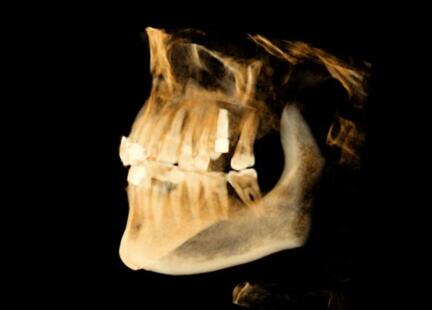

該系統(tǒng)用于口腔種植手術(shù)的術(shù)前計(jì)劃和術(shù)中引導(dǎo),通過對三維醫(yī)學(xué)影像的虛擬可視化應(yīng)用,采用專門的種植手術(shù)方案規(guī)劃軟件在三維模擬環(huán)境中進(jìn)行合理的種植方案設(shè)計(jì),結(jié)合精確的紅外光學(xué)定位技術(shù),實(shí)現(xiàn)手術(shù)器械、醫(yī)學(xué)影像和人體空間位置的融合。整個(gè)手術(shù)過程系統(tǒng)實(shí)時(shí)呈現(xiàn)病人解剖結(jié)構(gòu),全程監(jiān)控種植位點(diǎn)、角度、深度,從而實(shí)現(xiàn)精確種植。

運(yùn)用計(jì)算機(jī)三維重建與可視化技術(shù),清晰展現(xiàn)患者口內(nèi)解剖結(jié)構(gòu),保證了復(fù)雜病例的成功率。

術(shù)前種植體規(guī)劃